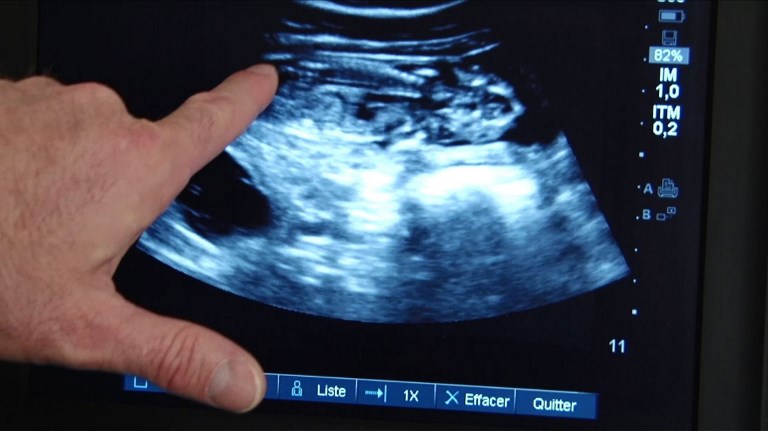

Un tratamiento de vitamina B3, presente de forma natural en la carne y en las verduras, podría prevenir los abortos espontáneos, debido al déficit de una molécula en el cuerpo, según un estudio científico australiano.

Su déficit en las mujeres embarazadas impide el buen desarrollo de los embriones, provocando abortos espontáneos o discapacidades de nacimiento en caso de que el embarazo prospere, según el estudio.